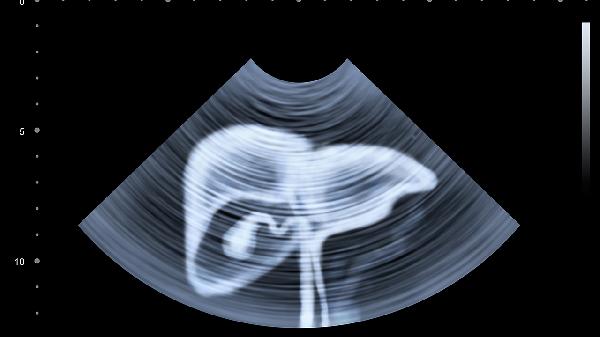

一、肝脏功能异常会拖累大脑

1、代谢废物堆积影响认知

肝脏负责分解体内毒素,当它的工作效率下降时,氨等有害物质会通过血液循环到达大脑,干扰神经细胞正常活动,出现类似"脑雾"的状态。